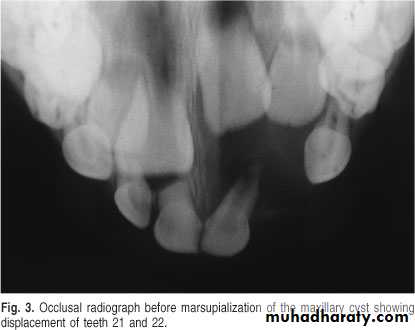

A 11-year-old female with swelling on the right side.

impacted canine